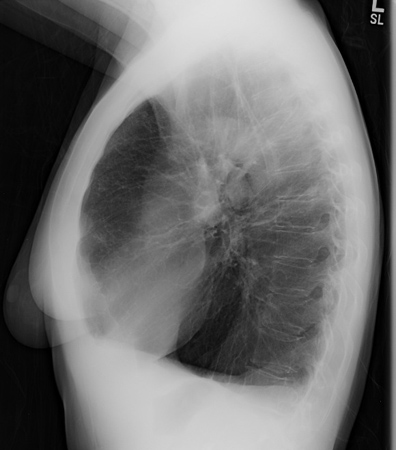

Radiografia torácica de deficiência de alfa 1-antitripsina (AAT) (visualização lateral)

Da coleção pessoal de D. Kyle Hogarth, MD, FCCP; usado com permissão